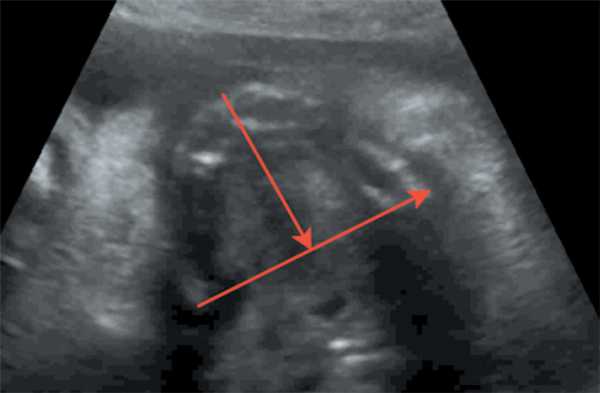

Рис. 6. Длина верхней челюсти / Fig. 6. Length of the upper jaw

Оценка развития челюстей также оценивалась по длине нижней челюсти — длина нижней челюсти в соотношении с биометрией плода (длиной бедренной кости). При измерении длины нижней челюсти проксимальным ориентиром становился височно-нижнечелюстной сустав. Увеличение длины нижней челюсти соотносится с увеличением срока гестации от 20 мм в 20 недель до 37 мм в 28 недель.